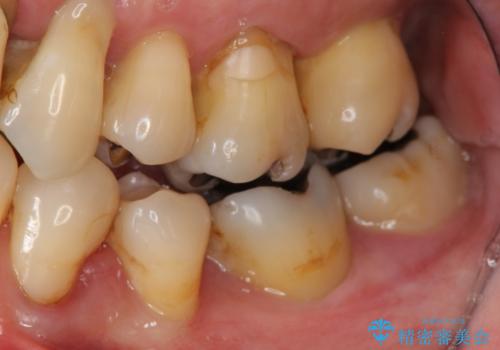

- 歯が全体的にグラグラし、しっかりと物が噛めなくなり歯周病治療を希望され来院されました。

残すことのできる歯、残すことのできない歯を初期治療を進めながら見極め、最終的に臼歯部はインプラント、上顎前歯は入れ歯による補綴計画となりました。